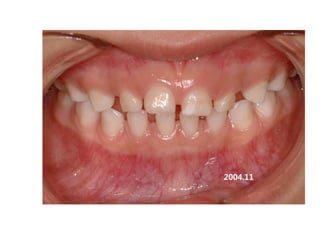

1999.11.24 /F

C.C

• Ant. crossbite, crowding

Dx

• Incorrect tongue posture and mentalis action

Goal

• Establish normal tongue posture and swallowing

pattern

2006.09.07

2006.10.27 Start T4K